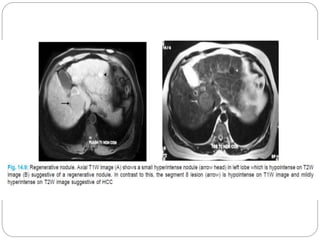

Hepatocellular carcinoma and regenerative nodule.

T1w MRI (A) and T2w MRI (B) demonstrating a hepatocellular

carcinoma (white arrowhead) and an adjacent atypical regenerative

nodule (black arrowhead).

MRI  Small HCC’sv/s regenerative  Cirrhotic nodule: hyper on T1 , hypo on T2  HCC : hypo on T1, hyperintense on T2 HCC arising in a siderotic nodule: “nodule within a nodule” appearance HCC - a small focus of high signal intensity within the low signal intensity nodule(T2).

• 33.

Hepatocellular carcinoma andregenerative nodule. T1w MRI (A) and T2w MRI (B) demonstrating a hepatocellular carcinoma (white arrowhead) and an adjacent atypical regenerative nodule (black arrowhead). Majority of hepatomas have decreased signal intensity on T1WI -increased signal -fat or glycogen content